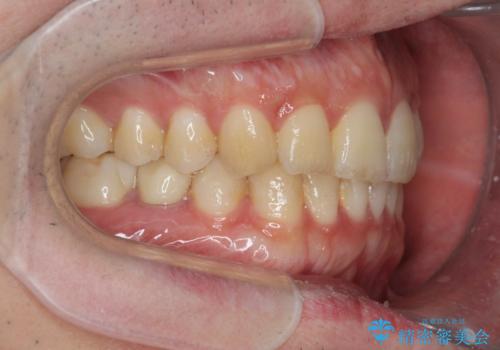

前歯のがたつきをなおしたい マウスピース矯正

- 気になる前歯のがたつきをきれいにしたい。と矯正治療を希望され来院されました。

大きな歯列の乱れはないため、倒れ込んでいる奥歯の傾きの改善、前歯のがたつきを改善する治療を計画します。

見た目が良くなっただけではなく、歯ブラシがしやすくなった!と治療後の歯並びに喜んでいただくことができました。